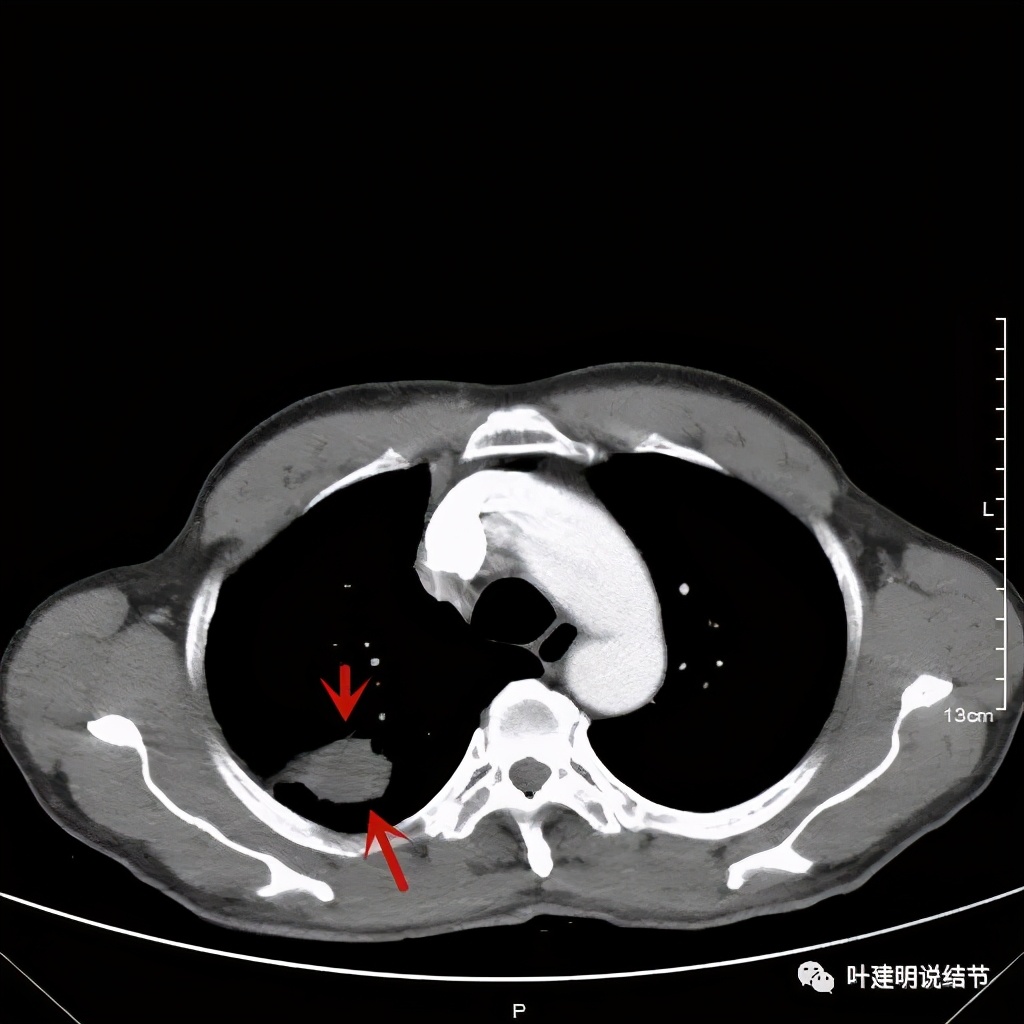

以上诸图是纵隔窗

总体上感觉,病灶比较大,不规则,不是圆形或圆形生长,周围有模糊磨玻璃影(考虑炎性渗出性?),虽有胸膜牵拉,但力度不够;增强有显著强化。病灶明显却无明显临床症状,普通感染是不像的,要么是结核,要么是肺癌。但肺癌的话,在2年前没有,2年内长到这么大,恶性程度应该很高,但其纵隔淋巴结却没有明显肿大。而且病灶的边缘部分过于光滑,没有见到肿瘤的细毛刺,膨胀性也不够。整体看病灶有点像“腰子”形,弯弯曲曲的。所以我的感觉更倾向结核性。查了肿瘤筛查指标如下: